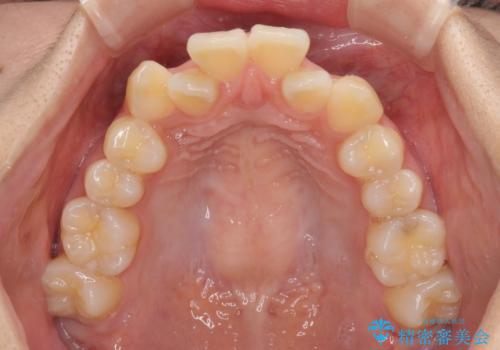

- 前歯のデコボコやクロスバイトと上顎の前突感による口の閉じにくさを気にして来院された患者様です。

目立たない装置を希望されたので、上顎が裏側装置のハーフリンガルを選択し、上下左右の小臼歯(計4歯)を抜歯して矯正治療を行うこととしました。